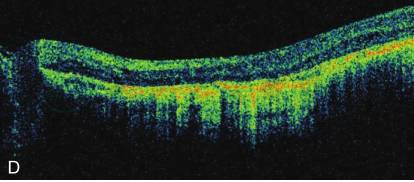

FFA表现RPE萎缩的窗样缺损,脉络膜毛细血管减少或消失,可以见到中等或大的脉络膜血管。最终当RPE和其上的视网膜被累及时,在周边视网膜上出现分散和成团的色素。FAF显示萎缩区低荧光,有高荧光线条围绕,且比眼底检查和彩色照相要敏感。OCT显示萎缩区内视网膜外层、RPE和脉络膜毛细血管缺失(图1)。ERG早期正常,晚期严重异常,甚至无波形。EOG早期就异常。血浆鸟氨酸含量检查无增高。

图1弥漫性脉络膜视网膜萎缩

A和B.双眼脉络膜视网膜萎缩,露出脉络膜大血管,呈黄色或白色;C和D.双眼OCT证实视网膜外层、RPE层和脉络膜全层萎缩